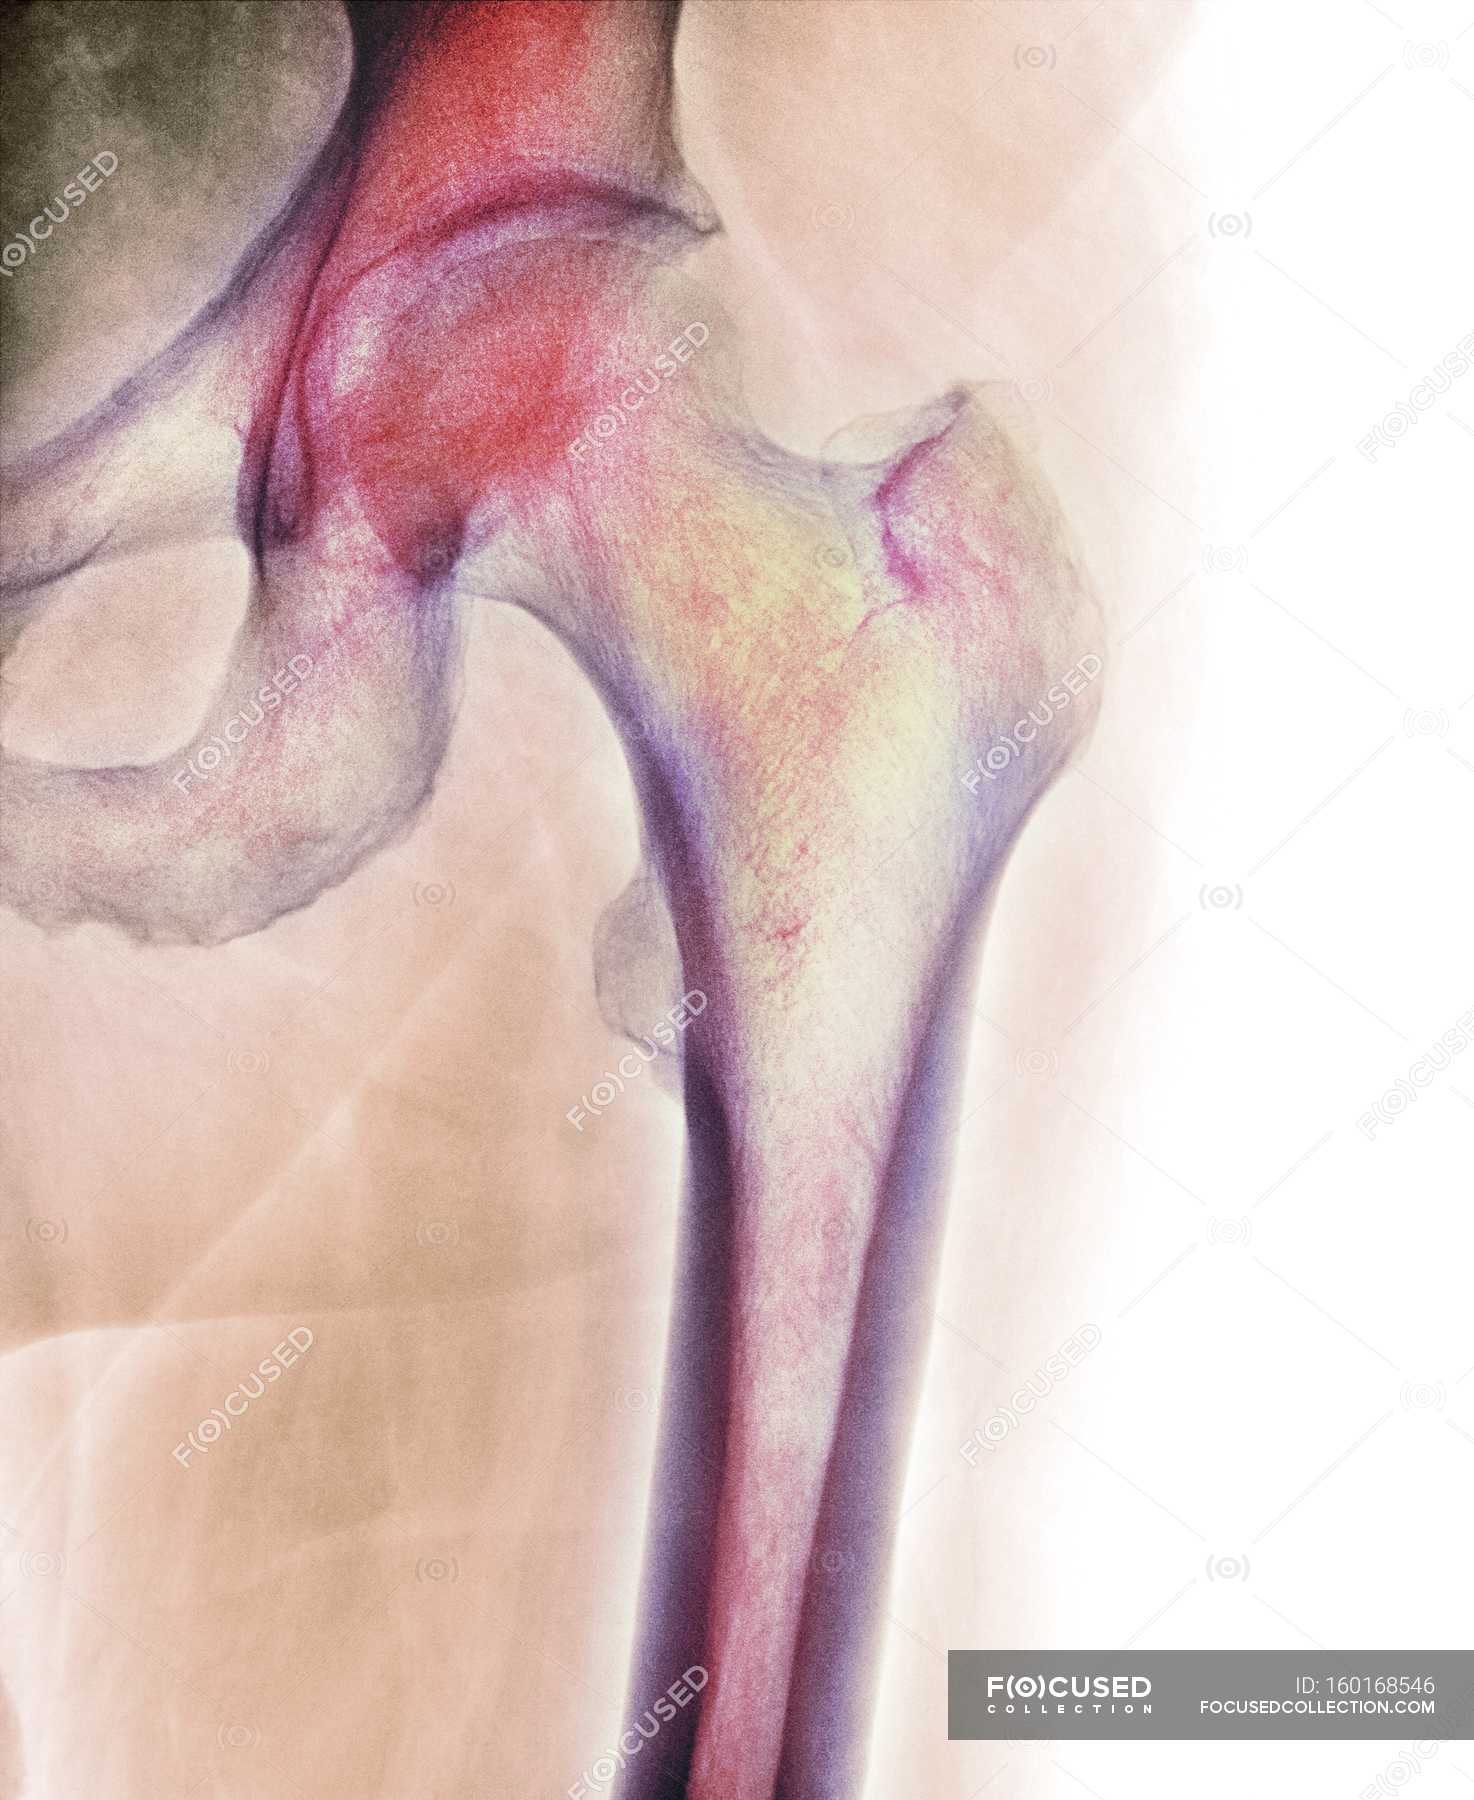

На рентгенограммах тазобедренный сустав сохраняет нормальную форму, суставная щель умеренно или неравномерно сужена с субхондральным склерозированием костных суставных поверхностей, непостоянными краевыми костными разрастаниями (I стадия).

У 116 (67.5%) пациентов имелись постоянные боли, иррадиирующие в бедро, паховую область, хромота, значительное ограничение движений, ограничение внутренней ротации и отведения, непостоянный хруст в суставе при движении.

Рентгенологически суставная щель может быть равномерно или неравномерно сужена, ацетабулярная суставная впадина уплощена, присутствуют явления субхондрального склероза, краевые костные разрастания. Конфигурация головки бедренной кости, как правило, не нарушена (II стадия).

В подавляющем большинстве случаев диагноз коксартроза ставится при рентгенографии, где видны изменения формы и структуры костей, составляющих тазобедренный сустав. Однако рентгенографически в ряде случаев затруднительно зафиксировать ранние проявления артроза, так как хрящевая ткань суставных поверхностей на рентгеновских снимках не отображается и мы можем судить о дегенеративном процессе, когда он достаточно выражен, вызывая изменения ширины просвета рентгеновской суставной щели.

КТ тазобедренного сустава проведено с 2002 года в 80, МРТ с 2011 года — в 22 случаях. Предпочтение следует отдать МРТ, так как при данном виде исследования можно четко визуализировать суставную капсулу и связки, идентифицировать даже поверхностные изменения хрящевого слоя, а также мелкие очаги субкортикального трабекулярного отека губчатого вещества костной ткани. КТ позволяет оценить минимальные изменения структуры и формы костной ткани, однако в общем объеме получаемой информации уступая МРТ в информативности. При углубленном обследовании для уточнения диагноза «коксартроз» и степени его выраженности можно рекомендовать проведение именно МРТ тазобедренных суставов.

На ранних стадиях диагностировать артроз можно только при проведении КТ или МРТ.

Остеофиты тазобедренного сустава даже на стадии запущенного коксартроза при визуальном обследовании не видны, поскольку сустав . Как лечить. Остеофиты склонны увеличиваться, если ничего не менять в распорядке дня, питании, уровне. Остеофиты тазобедренного сустава – это костные разрастания, которые препятствуют свободной подвижности нижней конечности, провоцируют развитие болевого синдрома. Патология развивается постепенно и имеет сложную природу. Сначала происходит постепенная деформация хрящевой ткани. Лечение остеофита тазобедренного сустава должно быть комплексным. Вследствие повреждения и уменьшения протеогликанов хрящ подсыхает, становится менее насыщенным водой. Остеофиты – патологически нарост на поверхности костной структуры, который возникает вследствие нарушения метаболизма кальция или заболеваний различной этиологии. 11 Остеофиты тел позвонков: что это такое. 12 Костные наросты тазобедренного сустава. 13 Что такое костные образования. . Остеофиты – это образования, которые могут развиваться, как после непосредственного повреждения костей, так и возникать на фоне тяжелых хронических заболеваний. Какое лечение поможет избавиться от остеофитов тазобедренного сустава? Диагноз коксартроз ставится на основании совокупности клинических симптомов и рентгенологических признаков.

Остеофиты склонны увеличиваться, если ничего не менять в распорядке дня, питании, уровне. Остеофиты тазобедренного сустава – это костные разрастания, которые препятствуют свободной подвижности нижней конечности, провоцируют развитие болевого синдрома. Патология развивается постепенно и имеет сложную природу. Сначала происходит постепенная деформация хрящевой ткани. Лечение остеофита тазобедренного сустава должно быть комплексным. Вследствие повреждения и уменьшения протеогликанов хрящ подсыхает, становится менее насыщенным водой. Остеофиты – патологически нарост на поверхности костной структуры, который возникает вследствие нарушения метаболизма кальция или заболеваний различной этиологии. 11 Остеофиты тел позвонков: что это такое. 12 Костные наросты тазобедренного сустава. 13 Что такое костные образования. . Остеофиты – это образования, которые могут развиваться, как после непосредственного повреждения костей, так и возникать на фоне тяжелых хронических заболеваний. Какое лечение поможет избавиться от остеофитов тазобедренного сустава? Диагноз коксартроз ставится на основании совокупности клинических симптомов и рентгенологических признаков. Уже на 1 стадии коксартроза на рентгеновском снимке обычно можно увидеть начальные остеофиты тазобедренного. Хирургическое лечение. Остеофиты колена, плеча, тазобедренного сустава. Болевой синдром. . Магнитно-резонансная томография. Лечение остеофитов колена, плеча, тазобедренного сустава. Остеофиты тазобедренного сустава. Рентгенологи цинично называют разрастания костной ткани шипами, пышными губами, грибовидными формами. Человек, на себе прочувствовавший, что такое остеофиты тазобедренного сустава, оперирует другими категориями: боль, малоподвижность, хромота. Остеоартроз тазобедренного сустава: степени заболевания. . Тазобедренный сустав – это крупное синовиальное сочленение шарнирного вида . На последних стадиях лечить консервативно патологически измененный сустав бесполезно. Лечение медикаментами. В борьбе с болью и воспалением в ТБС.

Уже на 1 стадии коксартроза на рентгеновском снимке обычно можно увидеть начальные остеофиты тазобедренного. Хирургическое лечение. Остеофиты колена, плеча, тазобедренного сустава. Болевой синдром. . Магнитно-резонансная томография. Лечение остеофитов колена, плеча, тазобедренного сустава. Остеофиты тазобедренного сустава. Рентгенологи цинично называют разрастания костной ткани шипами, пышными губами, грибовидными формами. Человек, на себе прочувствовавший, что такое остеофиты тазобедренного сустава, оперирует другими категориями: боль, малоподвижность, хромота. Остеоартроз тазобедренного сустава: степени заболевания. . Тазобедренный сустав – это крупное синовиальное сочленение шарнирного вида . На последних стадиях лечить консервативно патологически измененный сустав бесполезно. Лечение медикаментами. В борьбе с болью и воспалением в ТБС.